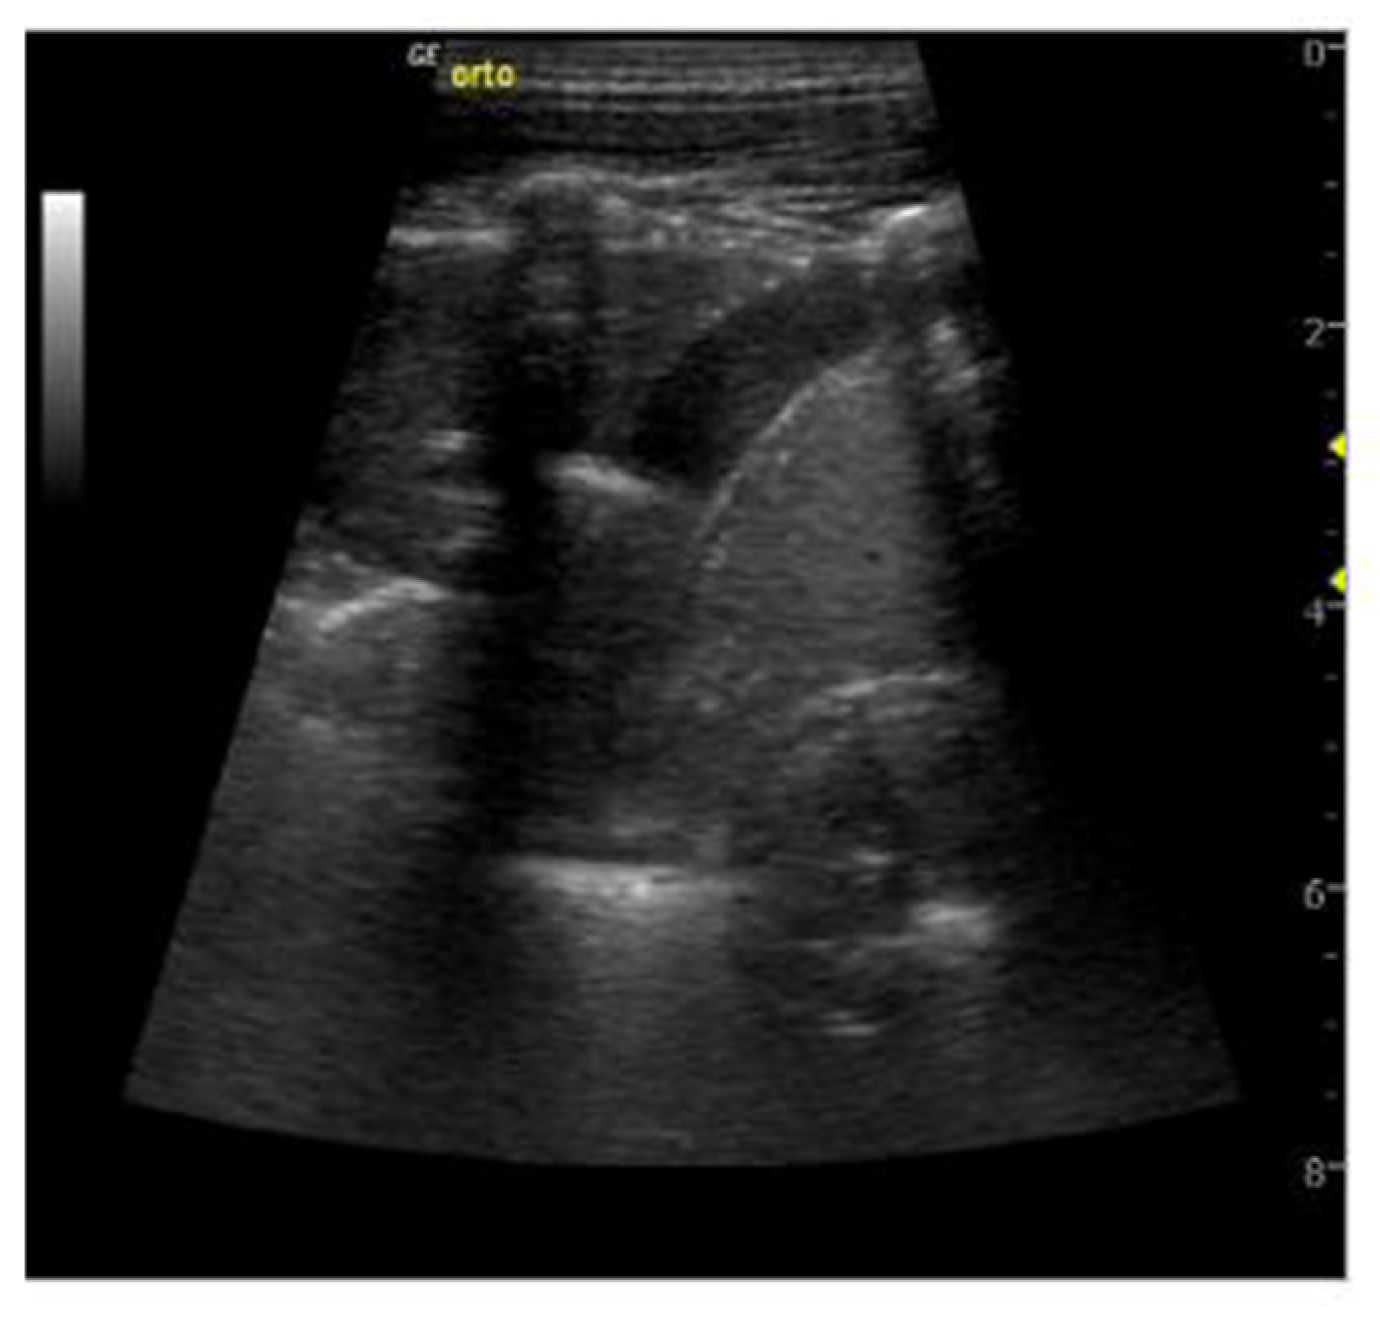

- Rea, G.; Sperandeo, M.; Lieto, R.; Bocchino, M.; Quarato, C.M.I.; Feragalli, B.; Valente, T.; Scioscia, G.; Giuffreda, E.; Foschino Barbaro, M.P.; et al. Chest Imaging in the Diagnosis and Management of Pulmonary Tuberculosis: The Complementary Role of Thoracic Ultrasound. Front. Med. 2021, 8, 753821. [Google Scholar] [CrossRef]

- Giannelli, F.; Cozzi, D.; Cavigli, E.; Campolmi, I.; Rinaldi, F.; Giachè, S.; Rogasi, P.G.; Miele, V.; Bartolucci, M. Lung ultrasound (LUS) in pulmonary tuberculosis: Correlation with chest CT and X-ray findings. J. Ultrasound 2022, 25, 625–634. [Google Scholar] [CrossRef]

- Cocco, G.; Boccatonda, A.; Rossi, I.; D’Ardes, D.; Corvino, A.; Delli Pizzi, A.; Ucciferri, C.; Falasca, K.; Vecchiet, J. Early detection of pleuro-pulmonary tuberculosis by bedside lung ultrasound: A case report and review of literature. Clin. Case Rep. 2022, 10, e05739. [Google Scholar] [CrossRef]